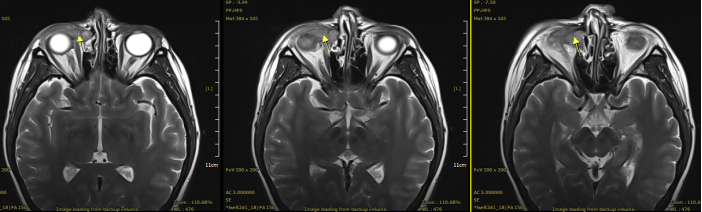

Figure 1: Pre-treatment (16mm × 22mm × 28mm)

General Information: A 44-year-old female patient presented with a round mass about the size of a mung bean at the root of the right nostril, accompanied by tearing. There was no redness, swelling, pain, significant secretion, visual impairment, headache, nausea, vomiting, orbital pain, diplopia, or visual distortion. The diagnosis was confirmed by orbital MRI, endoscopic biopsy of the right lacrimal sac tumor, and PET-CT.

Case Presentation: A 45-year-old female patient presented with a round mass about the size of a mung bean at the root of the right nostril, accompanied by tearing. There was no redness, swelling, pain, significant secretion, visual impairment, headache, nausea, vomiting, orbital pain, diplopia, or visual distortion. The diagnosis was confirmed by orbital MRI, endoscopic biopsy of the right lacrimal sac tumor, and PET-CT.